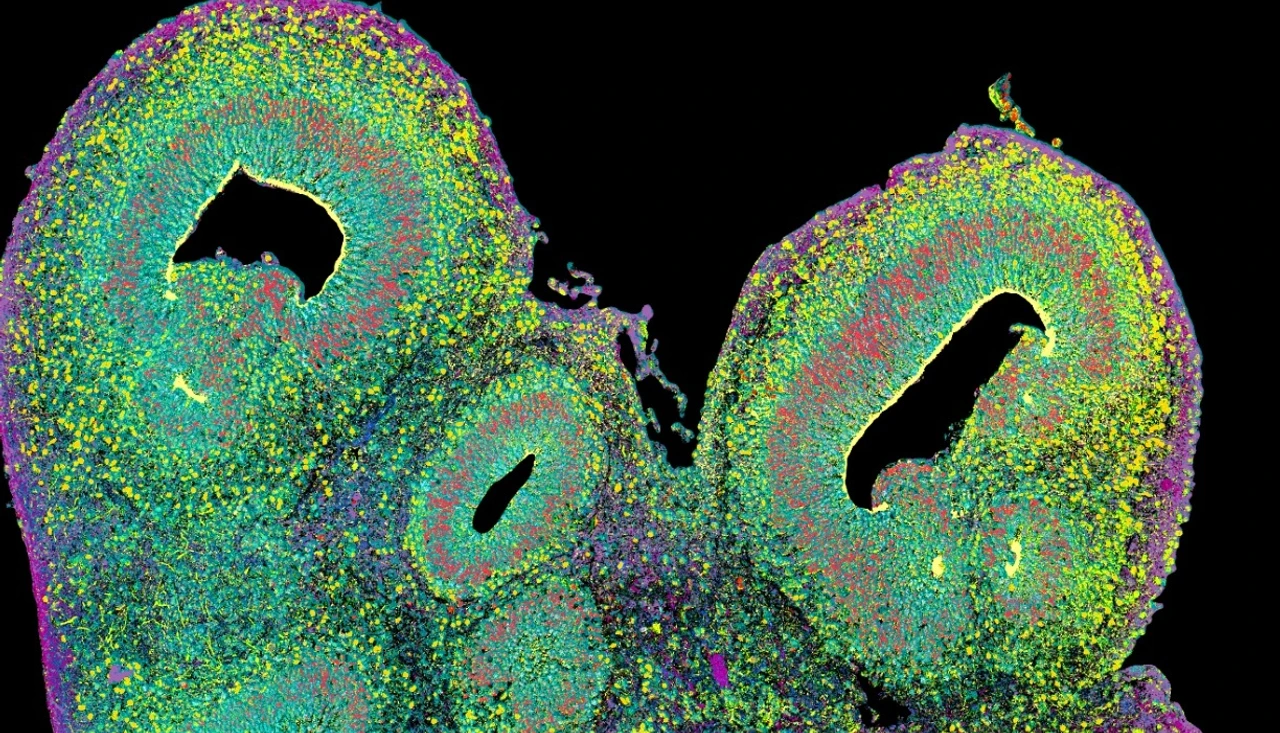

In a novel international study, researchers have created the Human Neural Organoid Cell Atlas (HNOCA), a comprehensive resource mapping the cellular diversity of human neural organoids. This atlas integrates 1.7 million single-cell transcriptomic profiles, offering a powerful tool for studying brain development, disease mechanisms, and organoid fidelity. In this interview, Prof. Fabian Theis talks about the significance of this new resource, its potential impact on neuroscience and medicine, and the crucial role of AI in building this resource.

Leveraging recent advances in AI, we integrated data from over 1.7 million single-cell transcriptomic profiles across 36 datasets. This resource allowed us to systematically assess the fidelity and variability of organoids compared to the developing human brain. Specifically, the HNOCA enables the comparison of organoid protocols with respect to represented brain regions and transcriptomic fidelity.

Neural organoids are tiny, lab-grown structures designed to mimic key features of the human brain. They are created from stem cells, which can develop into different types of cells in the body. Scientists use neural organoids to study brain development, investigate neurological diseases, and test potential treatments in a controlled, ethical setting.